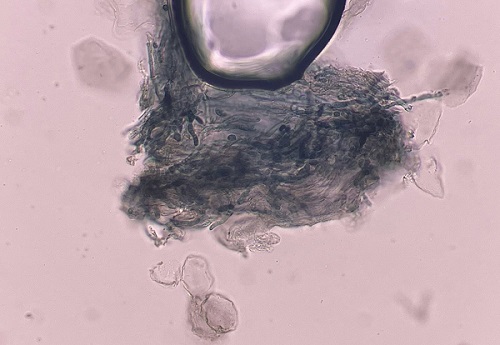

| Figura 2. Examen micológico directo con KOH de muestra de borde de lesión glútea, donde se observan hifas fúngicas septadas, ramificadas y de paredes finas, compatibles con dermatofitos del género Trichophyton |

El examen directo con hidróxido de potasio (KOH) puede ser positivo, detectando hifas y esporas. Sin embargo, puede ser insuficiente para distinguir dermatofitosis superficiales de las invasivas, dando resultados negativos incluso en casos de GM1,2,7. Series clínicas han mostrado que Trichophyton rubrum constituye el agente causal más frecuente, responsable de hasta dos tercios de los casos2,3.